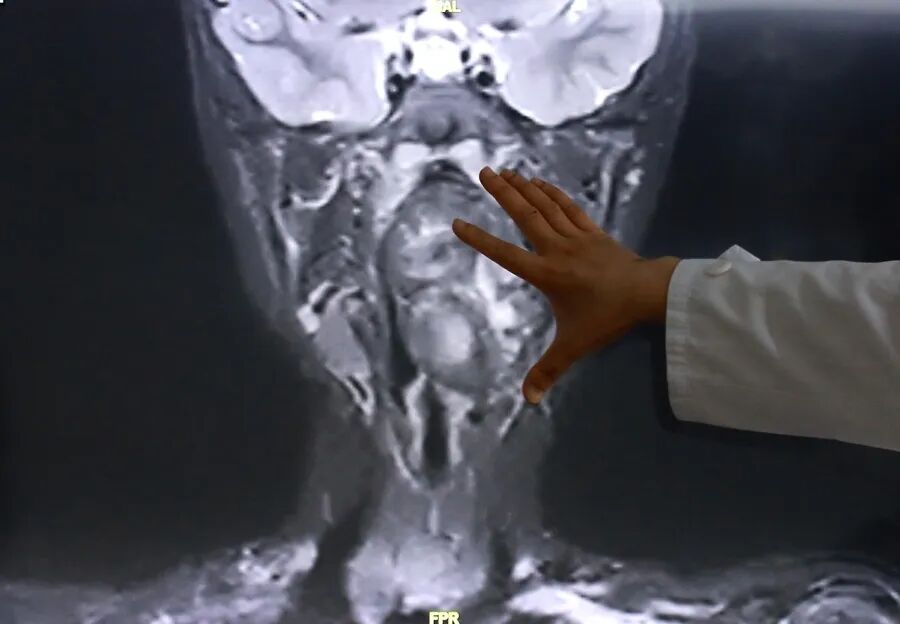

接诊后,综合前期检查及患儿家长自述病情,复旦儿科专家团队高度重视气道梗阻风险,立即启动复杂气道疾病绿色通道,完善增强CT及磁共振检查,明确小亮所患的肿瘤约7×3.5×3厘米,犹如“拳头”般大小。

专家表示,该肿瘤紧邻颈内动静脉并将血管明显向外推移,肿瘤向咽喉腔内隆起,占据大部分口咽及下咽腔,严重压迫声门,随时可能发生窒息。

复旦大学附属儿科医院耳鼻咽喉头颈外科副主任陈超表示,“我们可以看出它有脂肪,有软骨,这是一对双胞胎,一个是我们正常发育成的人,另外一个可能残留在这个咽旁间隙里面,就发育成了这样的一个畸胎瘤。”